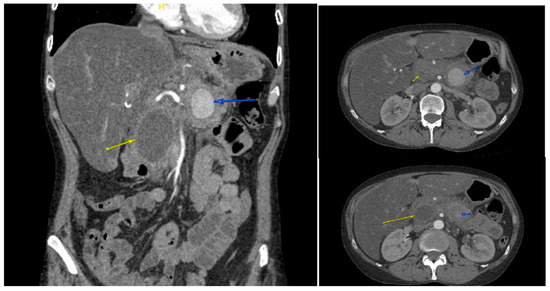

Background and Clinical Significance: Splenic artery pseudoaneurysm (SAP) is a rare but life-threatening complication of chronic pancreatitis. Although endovascular embolization achieves high technical success, recurrence and delayed rupture may occur, particularly in patients with ongoing pancreatic inflammation or alcohol use disorder (AUD). Case Presentation: A 47-year-old woman with alcohol-associated chronic pancreatitis presented with hematochezia, melena, and syncope. CT angiography revealed a 3.6 cm SAP adjacent to a 4.2 cm pancreatic head pseudocyst, and she underwent successful coil embolization. Despite initial stability, she relapsed into heavy alcohol use, experienced recurrent pancreatitis flares, and developed progressive multisystem comorbidities. Surveillance imaging up to three months post-embolization showed pseudocyst fluctuations without early recanalization, but long-term follow-up lapsed. Eight months after embolization, she presented in hemorrhagic shock from recurrent SAP rupture and died despite massive transfusion and emergent splenic artery ligation. Conclusions: Fatal SAP rupture may occur months after technically successful embolization. Sentinel bleeding, AUD relapse, and progressive systemic decline are critical warning signs. Structured post-embolization imaging and multidisciplinary management are essential to improve long-term outcomes. Full article

Figure 1